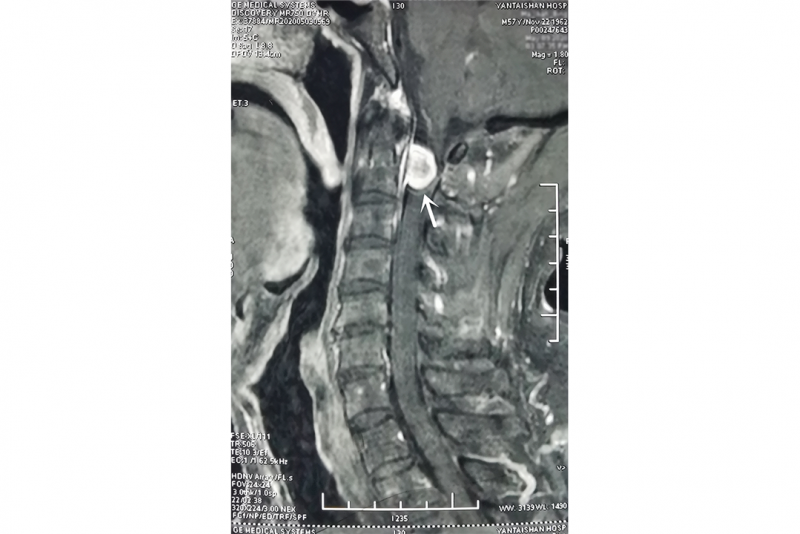

图中所示为马先生的寰枢椎椎管内肿瘤

近日,马先生来到烟台山医院脊柱外科就诊,接诊的烟台山医院原副院长沈炳华确诊他所患的是“寰枢椎椎管内肿瘤”。据悉,此处的肿瘤较为罕见,该肿瘤发病位置较高,毗邻有着“生命中枢”之称的延髓,且颈髓已严重受压。当时,马先生面临的风险较高,如果因行走不稳导致摔伤,很可能会因呼吸、心跳骤停而引发猝死。沈炳华建议他尽早接受手术治疗。